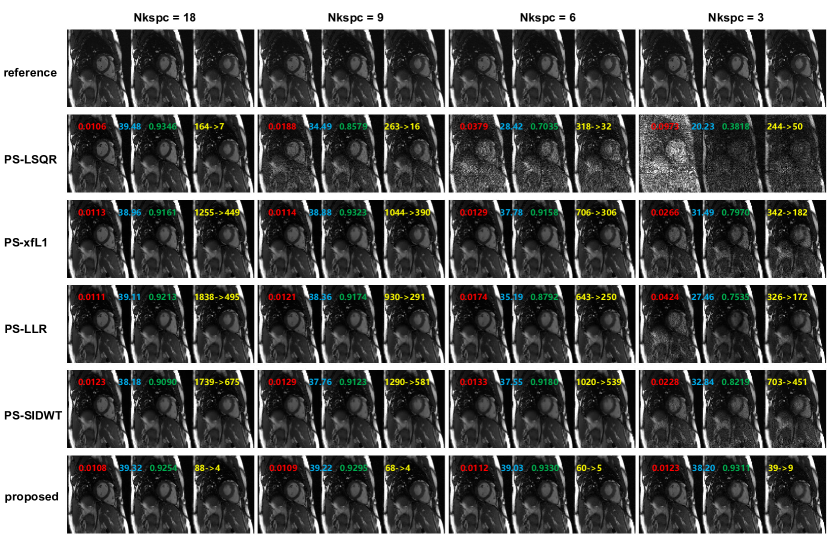

4.3.1 Comparative Study on Nkspc

The quality of PS model reconstruction is dependent on the total amount of “Imaging data”. More “Imaging data” leads to higher reconstruction quality, while at the expense of longer acquisition time. In this study, we use Nkspc to quantify the “Imaging data” amount, which denotes the number of full k-space if we neglect the phase encoding position and collect all the “Imaging data” compactly. Compared with total acquisition time, Nkspc is a better measurement of the difficulty for solving a PS model problem, because Nkspc is irrelevant of sequence TR, scan resolution, spatial coverage, and many other practical factors. Reconstruction experiments were performed on the retrospective dataset under Nkspc=18, 9, 6, 3. Quality metrics of nRMSE(normalized root mean square error), PSNR(peak signal to noise ratio), SSIM(structural similarity) were calculated based on the fully-sampled reference image, and the reconstruction time was recorded.

The reconstructed images for different Nkspc settings are shown in Figure 4. Under Nkspc=18, all the models produce similarly high quality images, with nRMSE slightly above 0.01, PSNR above 38 and SSIM above 0.90. When Nkspc is reduced to 9 and 6, the image quality of PS-LSQR model deteriorates obviously, while the performance of the other algorithms are only slightly affected. When the Nkspc is further reduced to 3, a notable image quality decline can be observed for the PS-xfL1, PS-LLR and PS-SIDWT methods. Only the proposed method can still keep good visual image quality. This suggests that the proposed method is the most stable algorithm when the acquisition time is significantly shortened. Besides, it can be observed that the operator optimization significantly reduces the computation time for all algorithms. The acceleration factor increases with the Nkspc value, which means more reconstruction time can be saved if the acquisition time is prolonged. For all Nkspc settings, the proposed method is always the fastest algorithm.